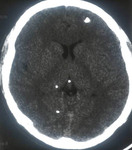

Cystic stage - neurocysticercosis: MRI scan showing cystic lesion in the frontal lobe; a scolex can be seen within the cyst

From the personal collections of Dr Christina Coyle and Dr Maheen Saeed; used with permission